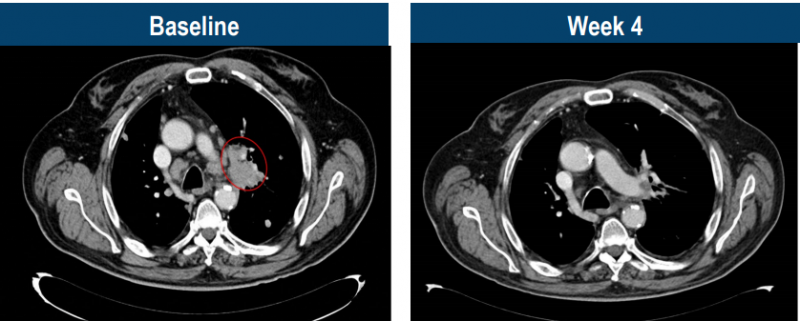

比如这位幸运的患者,69岁的M先生,被确诊为4期头颈癌,接受了化疗和PD-1治疗后病情仍不断进展,肿瘤转移至肺等多部位。幸运的是,经过检测存在MAGE-A4高表达,当50亿能够精准识别癌细胞的TCR-T大军回输到M先生体内后,仅4周,肿瘤快速消退,达到部分缓解!